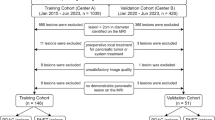

Thirty-eight patients (23 male, 15 female; age range 36–83 years, mean 55 years) diagnosed with a metastasized tumour of the gastrointestinal tract (n=23) or the pancreas (n=15) were included in this study. Histology of the primary had been obtained by resection (n=32), laparotomy (n=3) and needle biopsy (n=3).

All image fusion results were subject to visual plausibility control. Image fusion data of 2/38 patients (5%) were excluded from further analysis, as they did not pass plausibility control due to gross variations in the position of abdominal organs.

In the remaining 36 patients, SRS showed a total of 87 lesions. Table 1 lists their distribution according to clinical follow-up or histopathology.